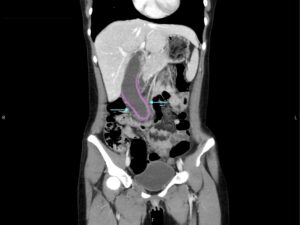

Hydropic Gallbladder. CT, Coronal, Annotated. JETem 2025

Hydropic Gallbladder. CT Coronal Annotated. JETem 2025